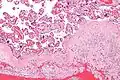

-

Scheme of placental circulation. -

Gross pathology of fetal membranes versus decidua